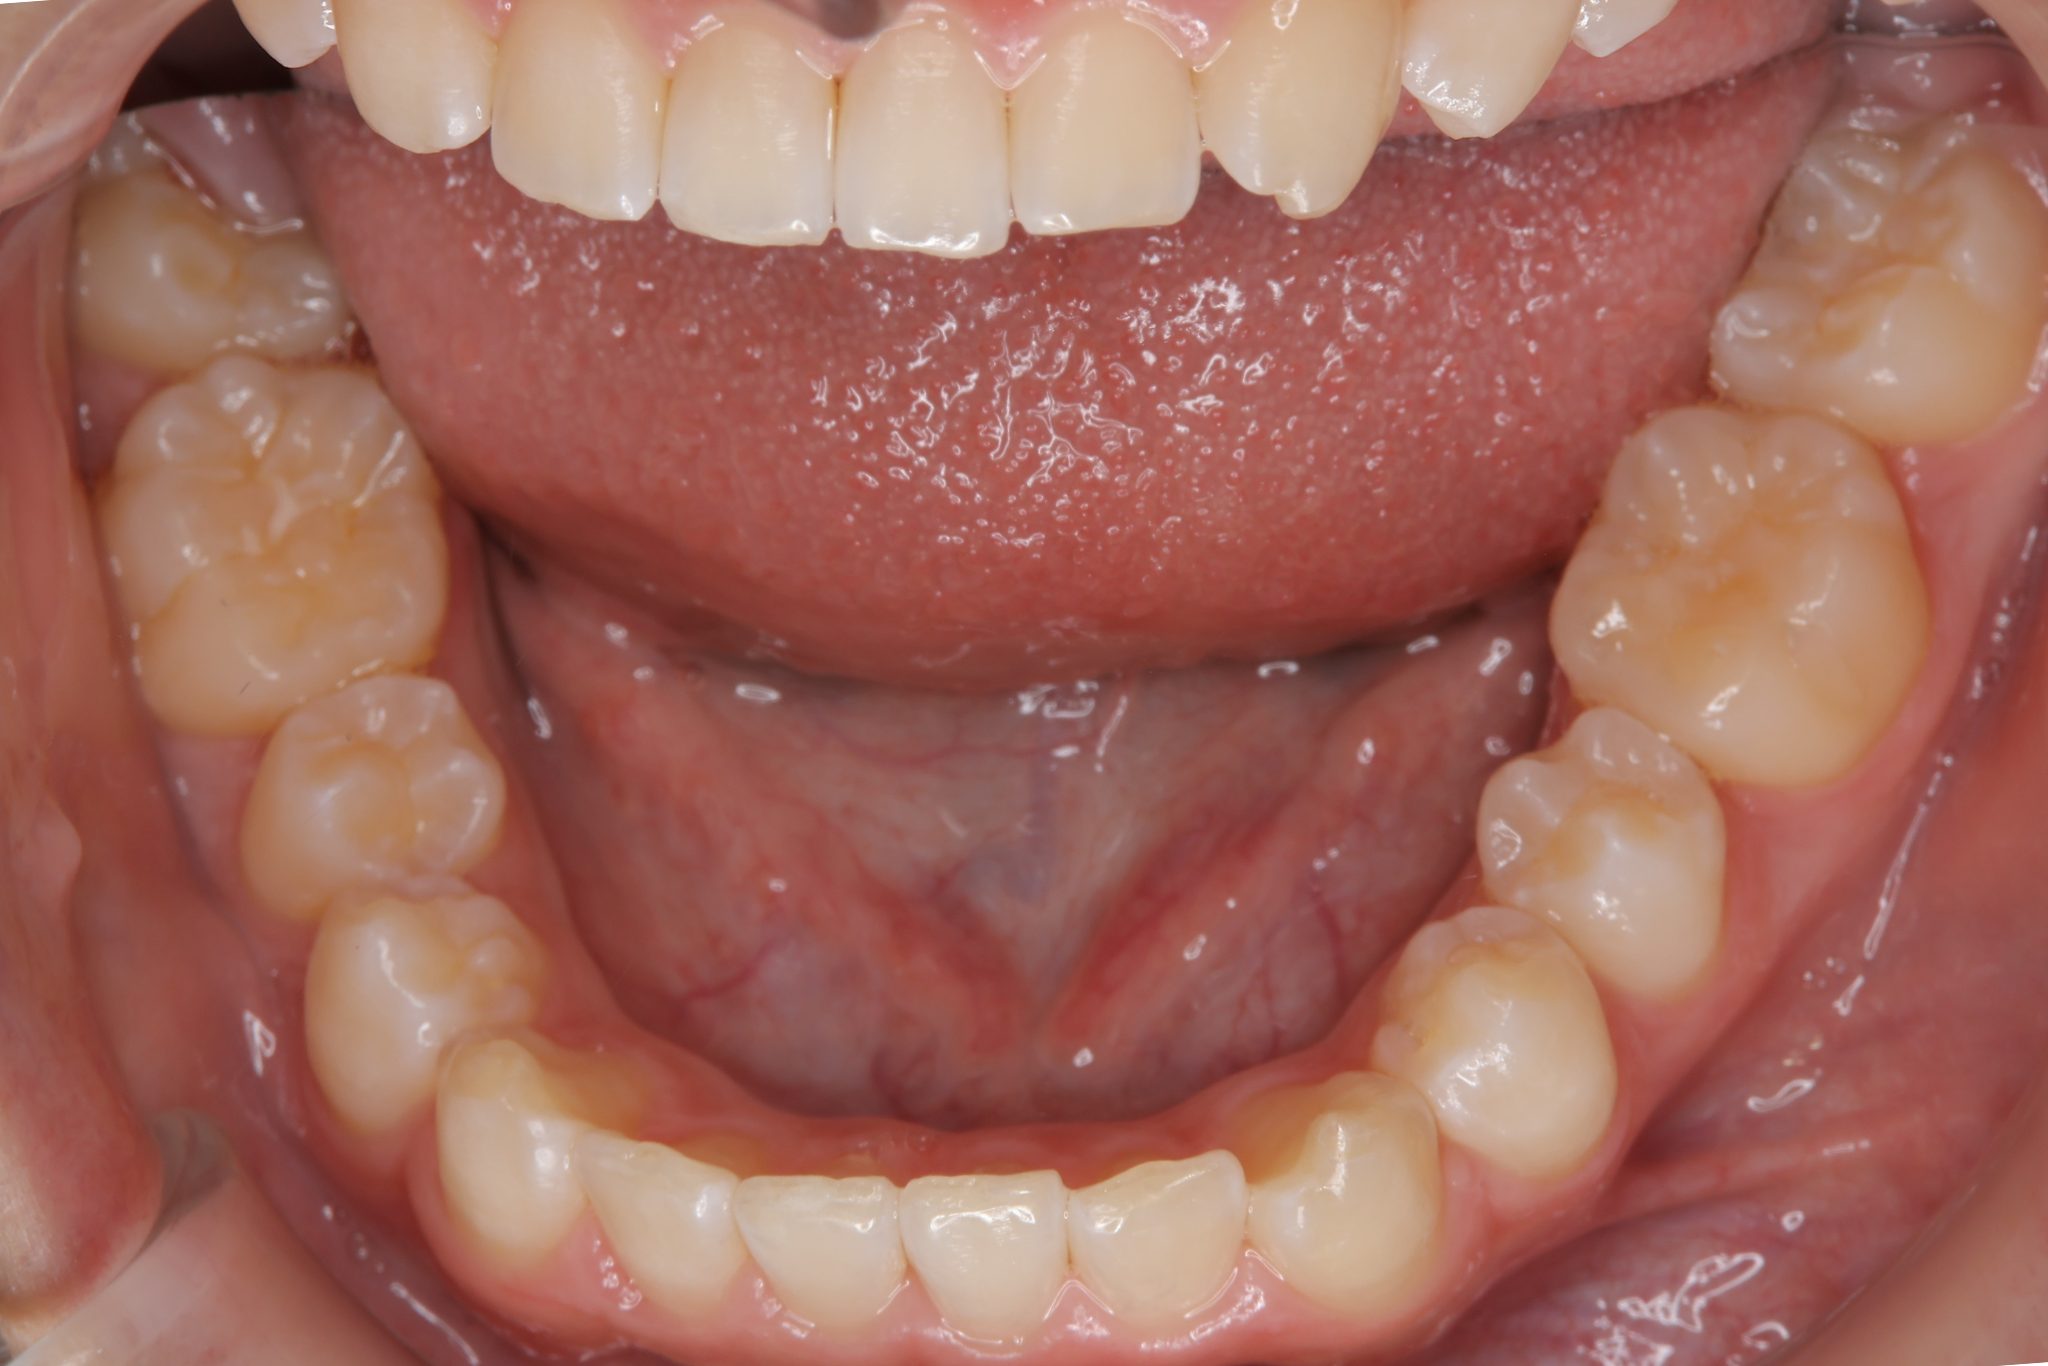

アフター

子どもの矯正治療|症例_121

施術内容 上顎急速拡大装置と下顎リンガルアーチを用いて上下顎骨を拡大した。

その後マウスピース型矯正装置で歯牙を配列し良好な咬合を獲得した。

治癒期間 3年11ヶ月間